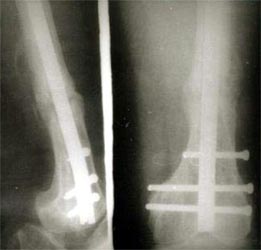

骨髓细胞与骨折愈合:骨髓中骨祖细胞可转化为成骨细胞,具有促进骨修复的作用,应用于临床也取得满意的效果。用髓内钉固定后保证早期稳定性,植骨补充成骨所需基质,骨髓骨祖细胞,可分化成为骨痂组织,骨生长因子促进骨折处再血管化,促进了骨不连的愈合。 病例介绍 病例一、患者63岁,股骨髁上骨折骨不连10年,曾先后4次手术,均采用钢板固定均松脱或折断而失败。 我们采用逆行髓内钉内固定,以及骨髓细胞复合生长因子植骨术,术后1年X线片连续性骨痂形成,膝关节功能良好。

病例二、患者33岁,股骨髁上骨折骨不连2年,曾用Ender’s钉固定断端不稳定,抗旋转性不足,钉移位退出失去固定作用而失败。我们采用逆行髓内钉内固定,以及骨髓细胞复合生长因子植骨术,术后1年X线片连续性骨痂形成,膝关节功能良好。